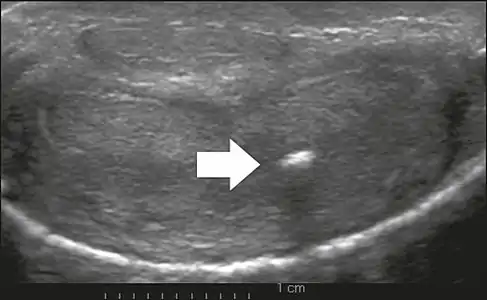

On penile ultrasonography, the typical appearance is hyperechoic focal thickening of the tunica albuginea. Due to associated calcifications, the imaging of patients with Peyronie's disease shows acoustic shadowing, as illustrated in figures below. Less common findings, attributed to earlier stages of the disease (still mild fibrosis), are hypoechoic lesions with focal thickening of the paracavernous tissues, echoic focal thickening of the tunica without posterior acoustic shadowing, retractile isoechoic lesions with posterior attenuation of the beam, and focal loss of the continuity of the tunica albuginea.

Transverse ultrasound of the penis, in a ventral view, in the middle portion of the penis. Note the echoic image with posterior acoustic shadowing, corresponding to calcification (arrow), in the left corpus cavernosum.[13]